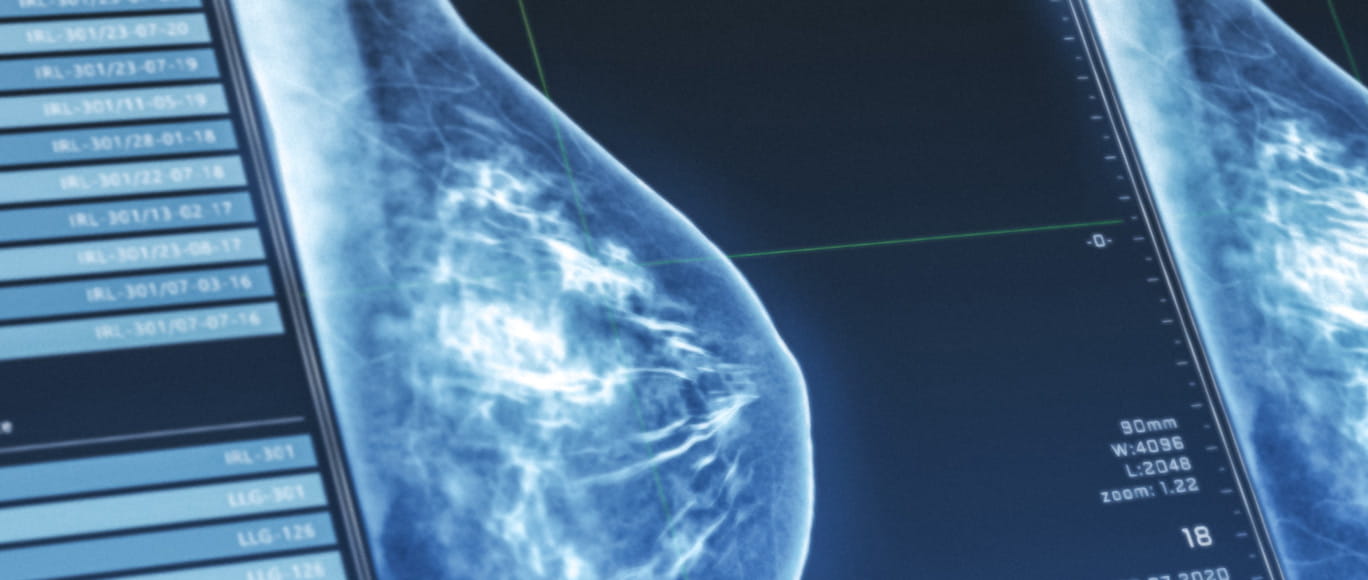

Our Comprehensive Breast Care Centers

From diagnosis to survivorship, the fellowship-trained breast surgeons, board-certified medical oncologists and experienced nurse navigators at BayCare's Comprehensive Breast Care Centers provide access to advanced treatment options, clinical trials and a supported care journey to enhance outcomes for patients experiencing breast health concerns.